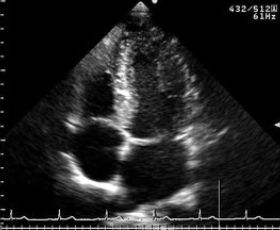

超音波診断装置 乳腺超音波検査 心臓超音波検査

ARIETTA 850

⑤ 超音波検査

乳腺・甲状腺(良性および悪性腫瘤・その他異常所見の有無)、頸動脈(動脈硬化等による血管の

詰まりや血流)、心臓(弁を含めた心臓の動き)を画像として捉え検査します。また、女性技師による乳がんドック(乳腺超音波検査)行っております。詳しくはこちら